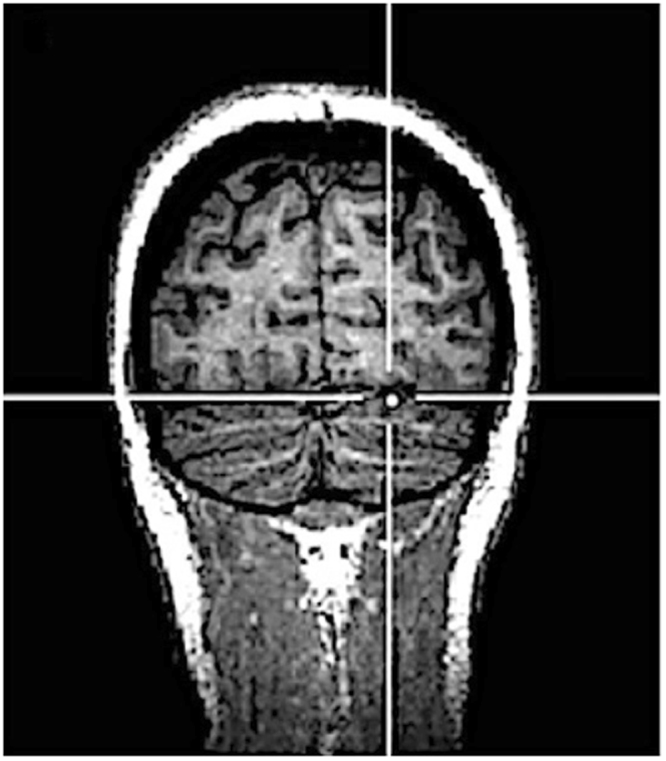

Triple-pulse 20 Hz TMS was delivered 150 ms before the presentation of the last stimulus of the test sequence (so that the last TMS pulse was given 50 ms before the onset of the stimulus), with similar parameters of stimulation used in previous TMS studies targeting the cerebellum28,30–32. TMS was delivered over the right cerebellum, the early visual cortex and the vertex (control condition). Early visual cortex was chosen as additional control area since prior evidence suggests that cerebellar stimulation may spread to primary visual cortex33. The cerebellum and the early visual cortex were localized by means of stereotaxic navigation on individual estimated magnetic resonance images (MRI) obtained through a 3D warping procedure fitting a high-resolution MRI template with the participant’s scalp model and craniometric points (Softaxic, EMS, Bologna, Italy). This procedure has been proven to ensure a global localization accuracy of about 5 mm, a level of precision closer to that obtained using individual MRI scans34, and has been successfully used in many prior studies35–37. Anatomical Talairach coordinates38 used for neuronavigation were x = 22, y = −75, z = −21 for the right cerebellum (corresponding to cerebellar loci of activation reported in a previous neuroimaging study investigating processing of visual sequences violation15, see Fig. 2) and x = −2, y = −81.4, z = 1.4 for early visual cortex39. The region effectively affected by cerebellar TMS corresponded to the superficial layers of the cerebellar cortex40,41: in fact, deeper sites were unlikely to be directly reached by the stimulation as the intensity of the electrical field induced by TMS drops dramatically as a function of the distance from the coil42. The vertex was localized as the point falling half the distance between the nasion and the inion on the same43,44 midline. The coil was placed tangentially to the scalp and held parallel to the midsagittal line, with the handle pointing backward in the vertex and with the handle pointing superiorly in the cerebellum and early visual cortex TMS stimulation.

Figure 2.

Anatomical Talairach coordinates of the targeted cerebellar site (x = 22, y = −75, z = −21).